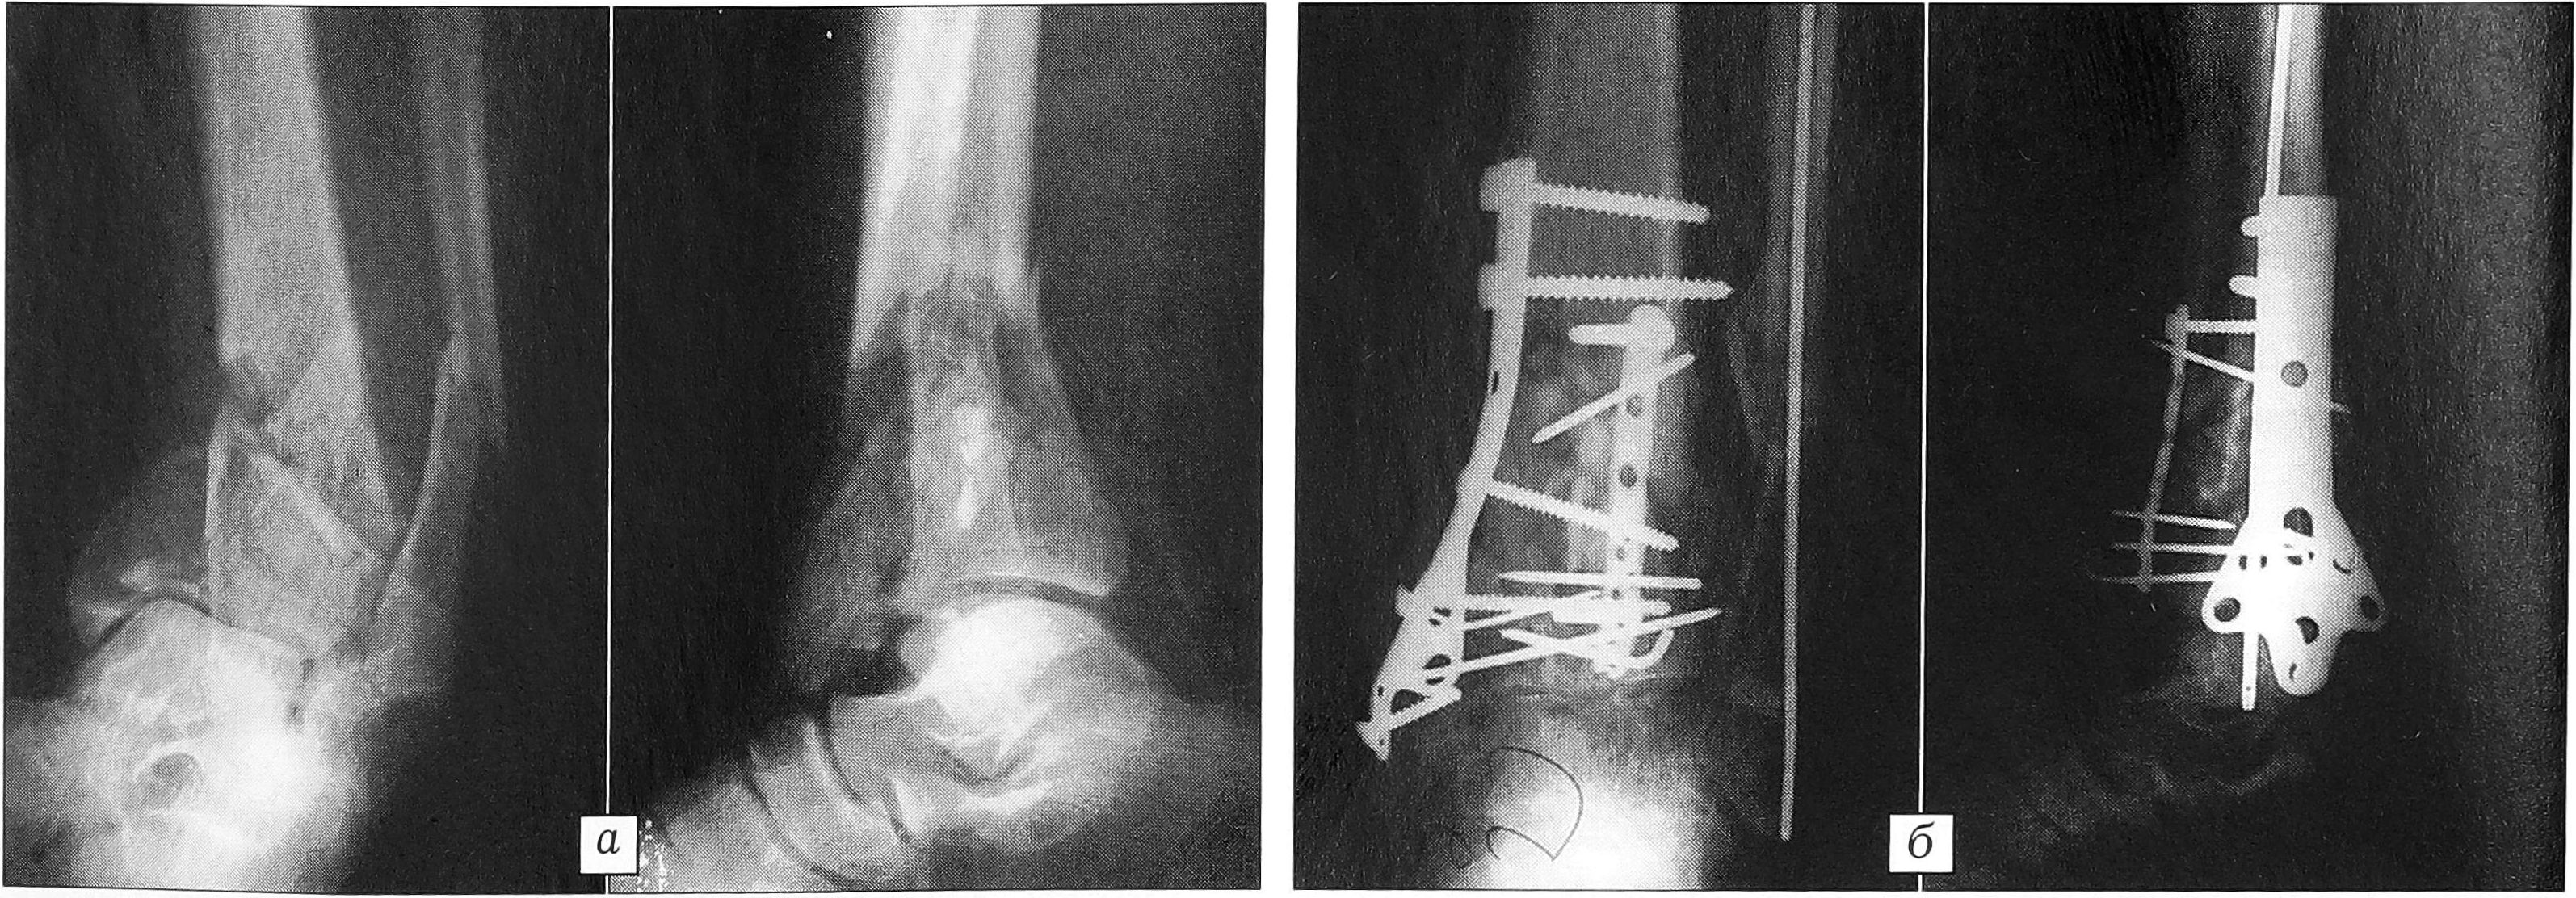

В качестве примера приводим рентгенограммы двух больных (рис. 2 и 3).

Рис. 2. Рентгенограммы больного Б. 51 года. Многооскольчатый компрессионный перелом дистального метаэпифиза большеберцовой кости (вариант Д). а — до операции; б — после остеосинтеза реконструктивной и Т-образной пластинами.